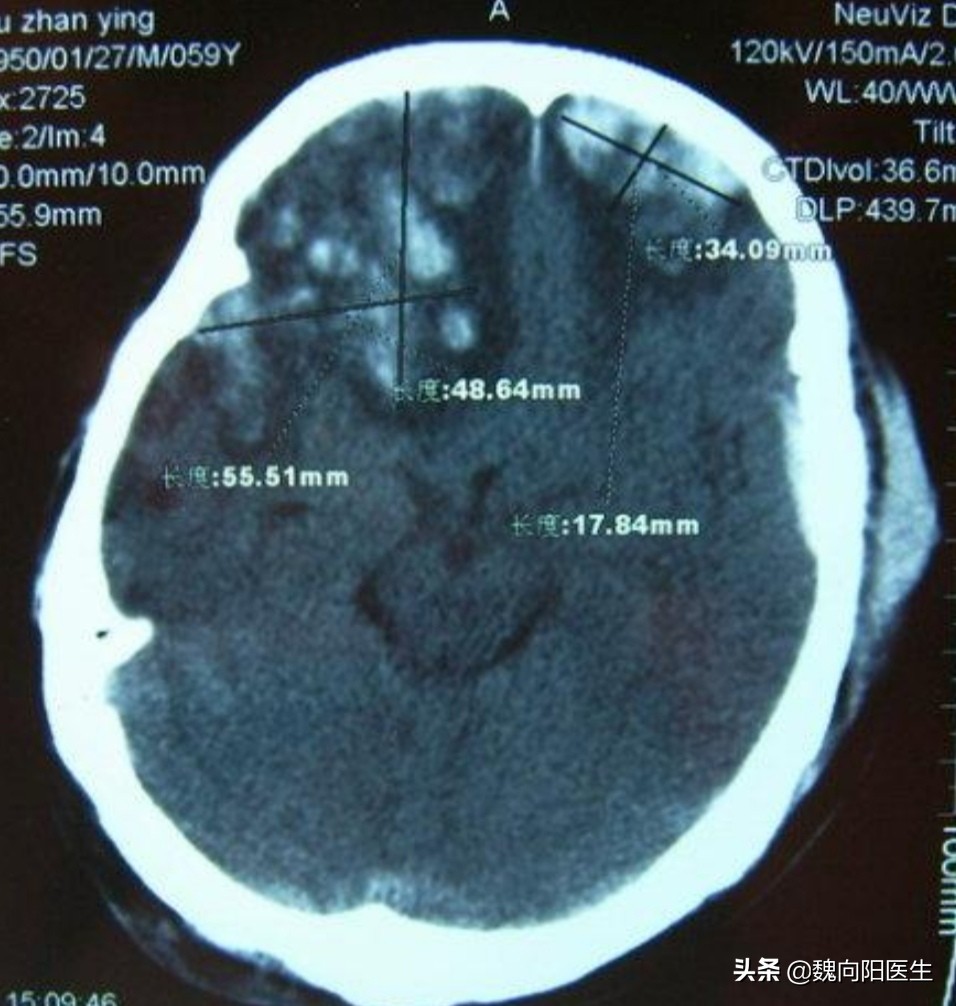

一般撞到头部后脑勺,很多脑出血是发生在前额或前颅底部位。这叫做对冲伤。

早期出现脑额颞叶挫裂伤

对冲伤(contre-coup injury):头部受外力作用时,于着力处的对侧部位的脑组织发生损伤,称为对冲伤。对冲伤多见于头颅撞击外界物体而致伤者,少见于受打击致伤者,即减速运动多见。

由于前颅底骨头表面不光滑,且神经组织众多,在后枕部受到撞击后,导致脑组织在不光滑颅骨表面滑动,从而导致脑挫裂伤、硬膜下血肿或蛛网膜下腔出血可能。